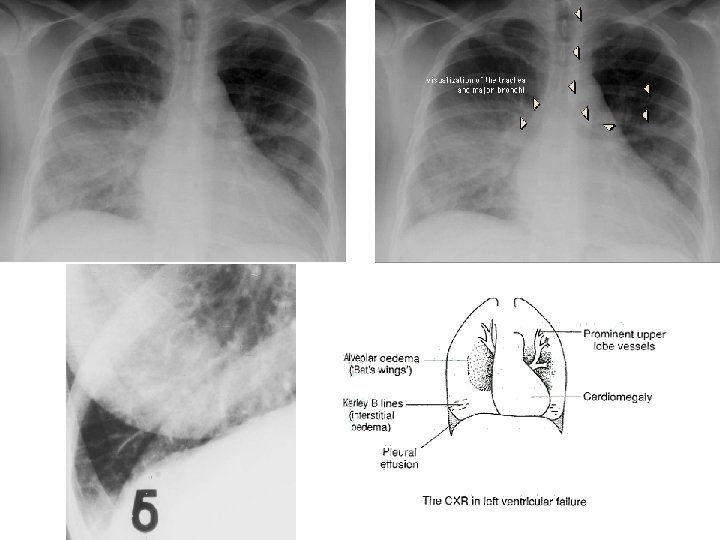

ACUTE PASSIVE HYPEREMIA/CONGESTION, LUNG

Kerley B Air Bronchogram

CHRONIC PASSIVE HYPEREMIA/CONGESTION, LUNG